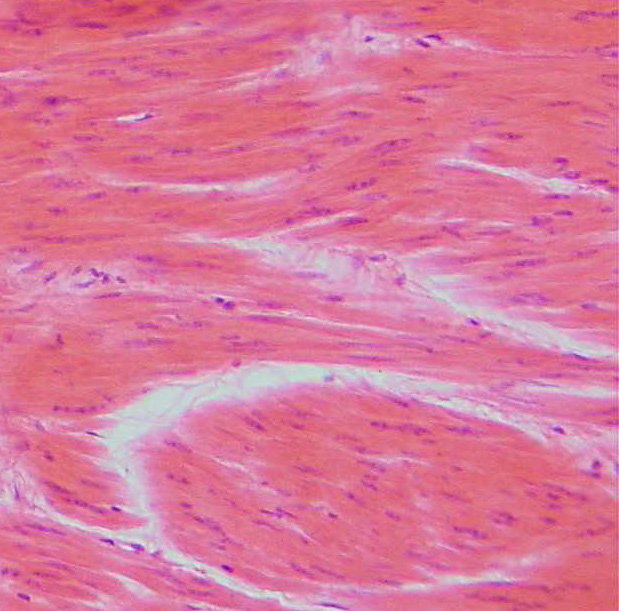

Leiomyosarcoma is a type of cancer of the smooth muscles that can arise almost anywhere in the body. Common places are the uterus, the abdomen or the muscles of the blood vessels. Even the tiny muscles that make our hair stand on end can be affected.